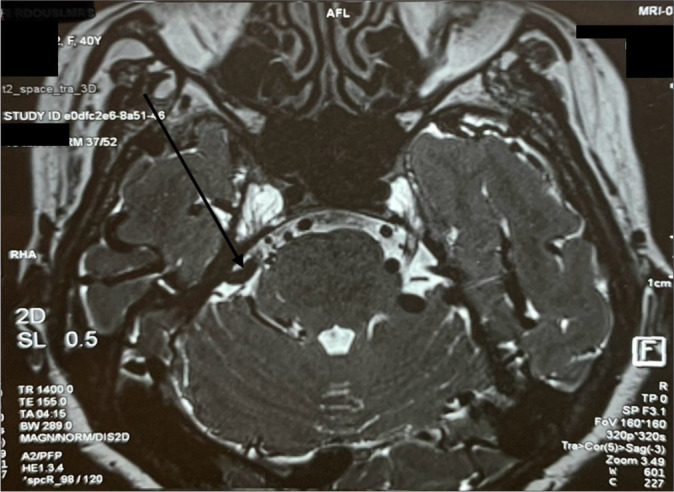

Case description: We report a case of a 40-year-old female suffering from debilitating right-sided facial pain due to a rare "scissor effect" produced by the superior petrosal sinus and Dandy's vein (vein of the cerebellomesencephalic fissure) compressing the trigeminal nerve. Surgical decompression was performed by interposing autologous skeletal muscle wrapped with Surgicel between the conflicting venous structures and the nerve. The patient achieved complete pain relief without neurological deficits.